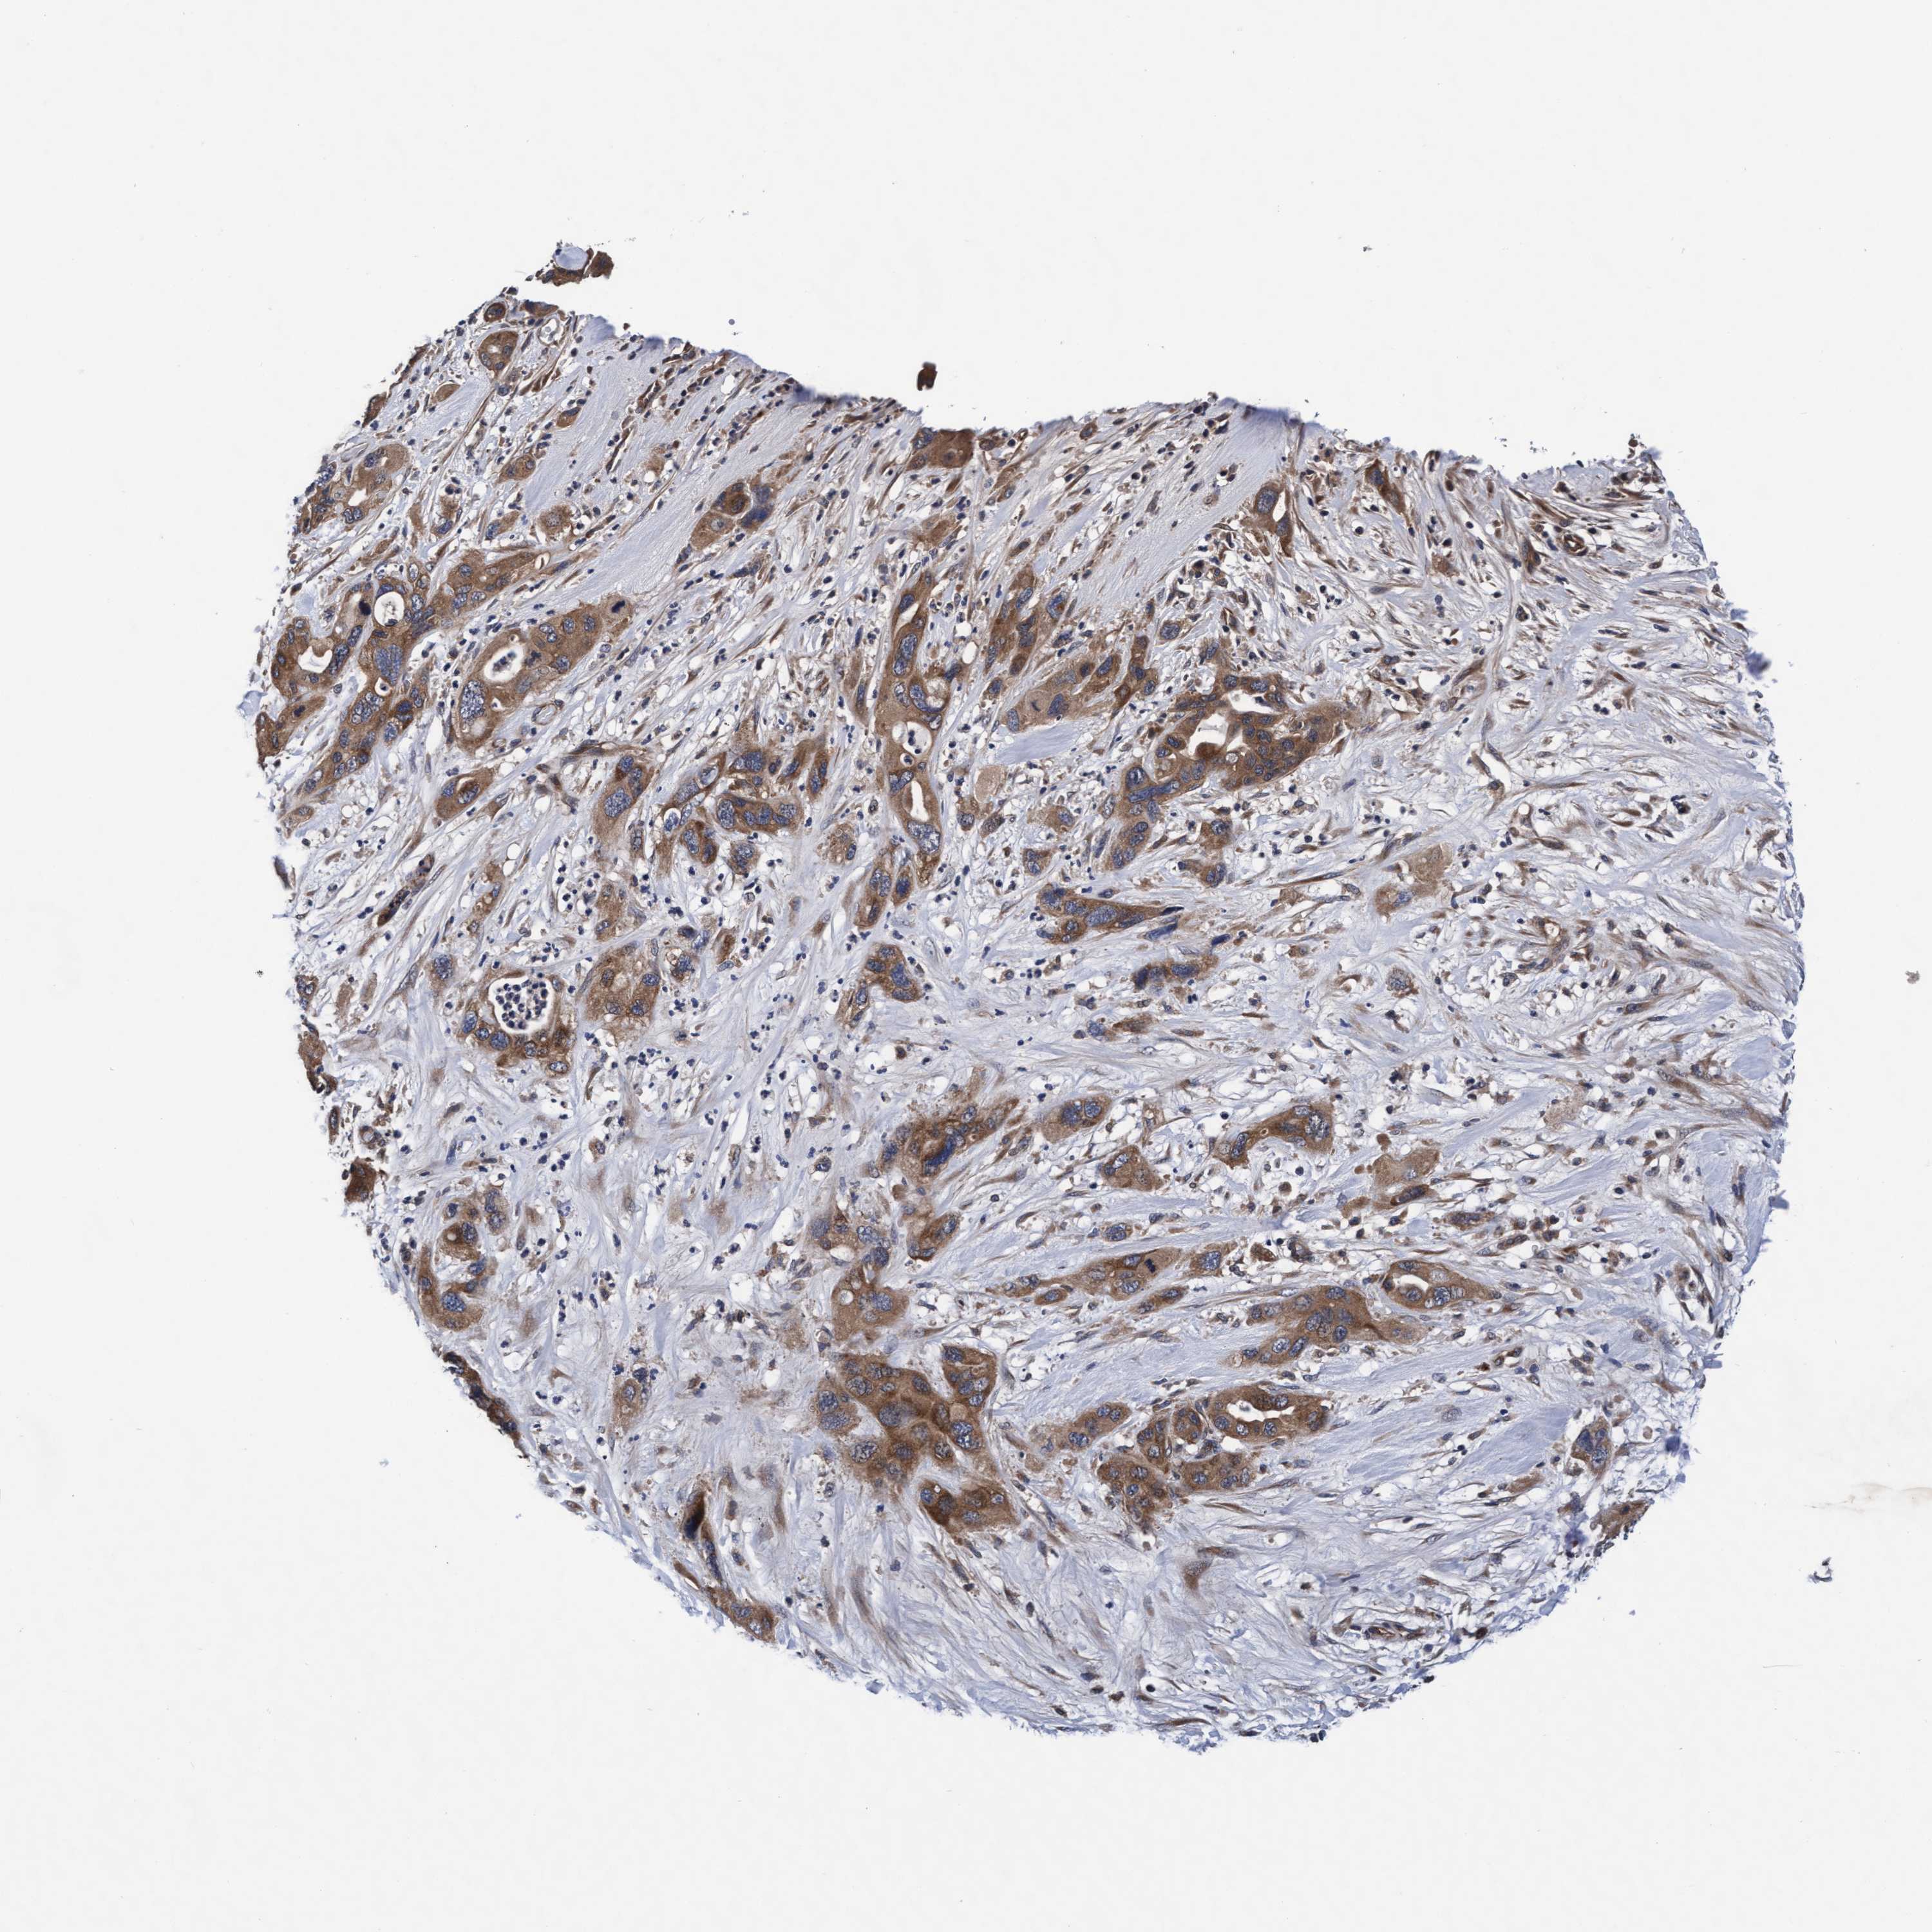

PANCREATIC CANCER - Protein expressioni

A mouse-over function shows sample information and annotation data. Click on an image to view it in a full screen mode. Samples can be filtered based on level of antibody staining by selecting one or several of the following categories: high, medium, low and not detected. The assay and annotation is described here.

Note that samples used for immunohistochemistry by the Human Protein Atlas do not correspond to samples in the TCGA dataset.

Antibody stainingi

Antibody staining in the annotated cell types in the current human tissue is reported as not detected, low, medium, or high, based on conventional immunohistochemistry profiling in selected tissues. This score is based on the combination of the staining intensity and fraction of stained cells.

Each image is clickable and will lead to virtual microscopy that enables deeper exploration of all samples and also displays staining intensity scores, fraction scores and subcellular localization as well as patient and tissue information for each sample.

Antibody HPA021633

Antibody HPA023249

Antibody HPA026561

Antibody CAB002501

Staining

High

Medium

Low

Not detected

Intensity

Strong

Moderate

Weak

Negative

Quantity

>75%

75%-25%

<25%

None

Location

Nuclear

Cytoplasmic/membranous

Cytoplasmic/membranous,nuclear

Adenocarcinoma, NOS

Adenocarcinoma, metastatic, NOS